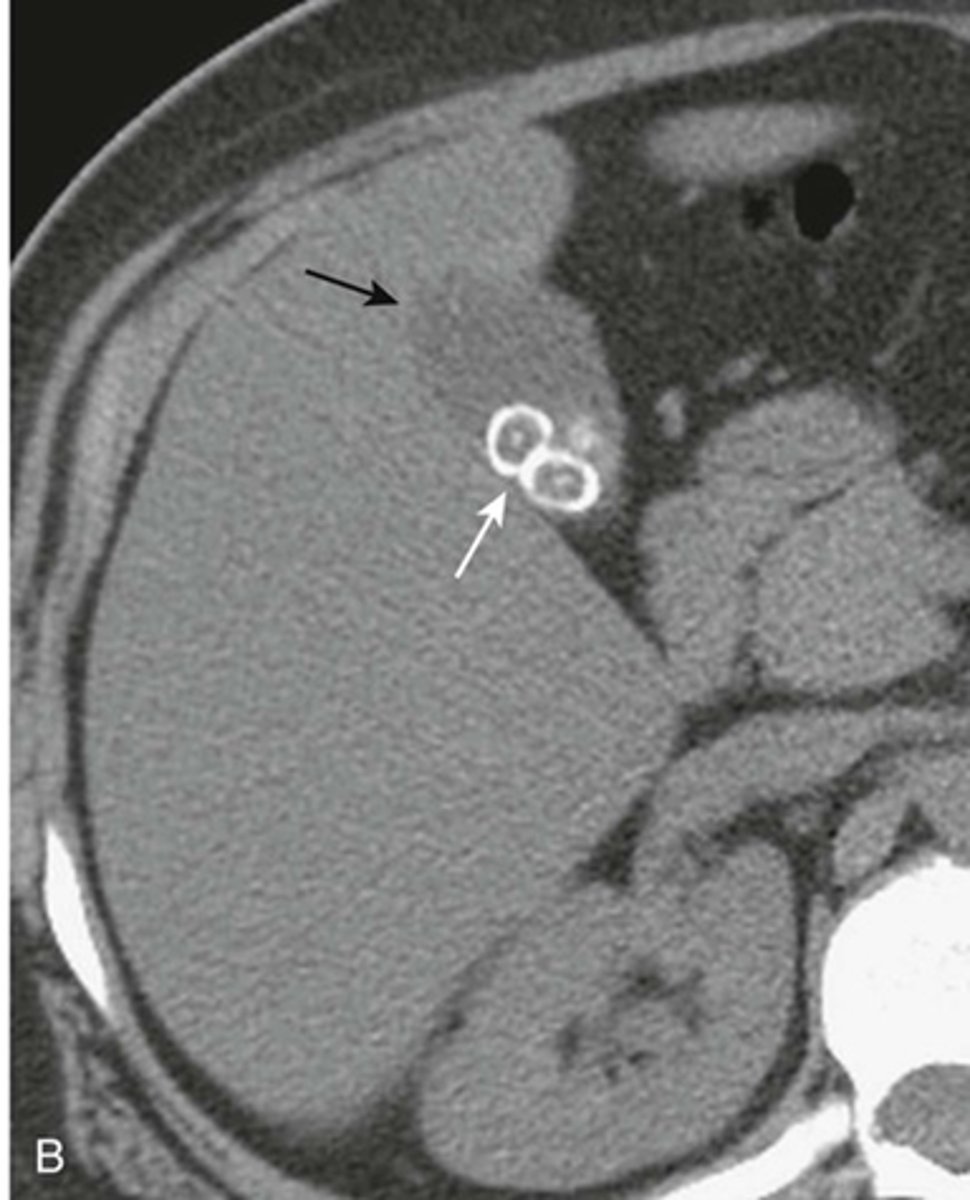

Calcified gallbladder wall.

WHITE ARROW: rimlike calcification on wall of a cyst or saccular organ.

This is a porcelain gallbladder - occurs with chronic inflammation and stasis.

associated with gallstones in over 90% of cases and an increased incidence of carcinoma of the gallbladder in about 20% of cases.